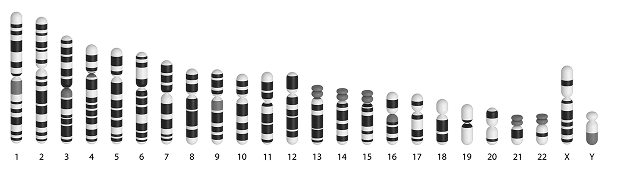

| 3種トリソミー21, 18, 13 | |||

| 全染色体異数性1〜22番染色体 | |||

| 性染色体異常X, Y染色体 | |||

| モノソミーXターナー症候群 | |||

| トリプルX症候群XXX | |||

| クライン フェルター症候群(XXY) |

|||

| ヤコブ症候群XYY | |||

| 微小欠失症候群 | |||

| 1p36欠失症候群 | |||

| 4p欠失症候群Wolf-Hirschhorn | |||

| 5p欠失症候群猫鳴き症候群 | |||

| 15q11.2欠失症候群Prader-Willi/ Angelman |

|||

| 22q11.2欠失症候群DiGeorge |